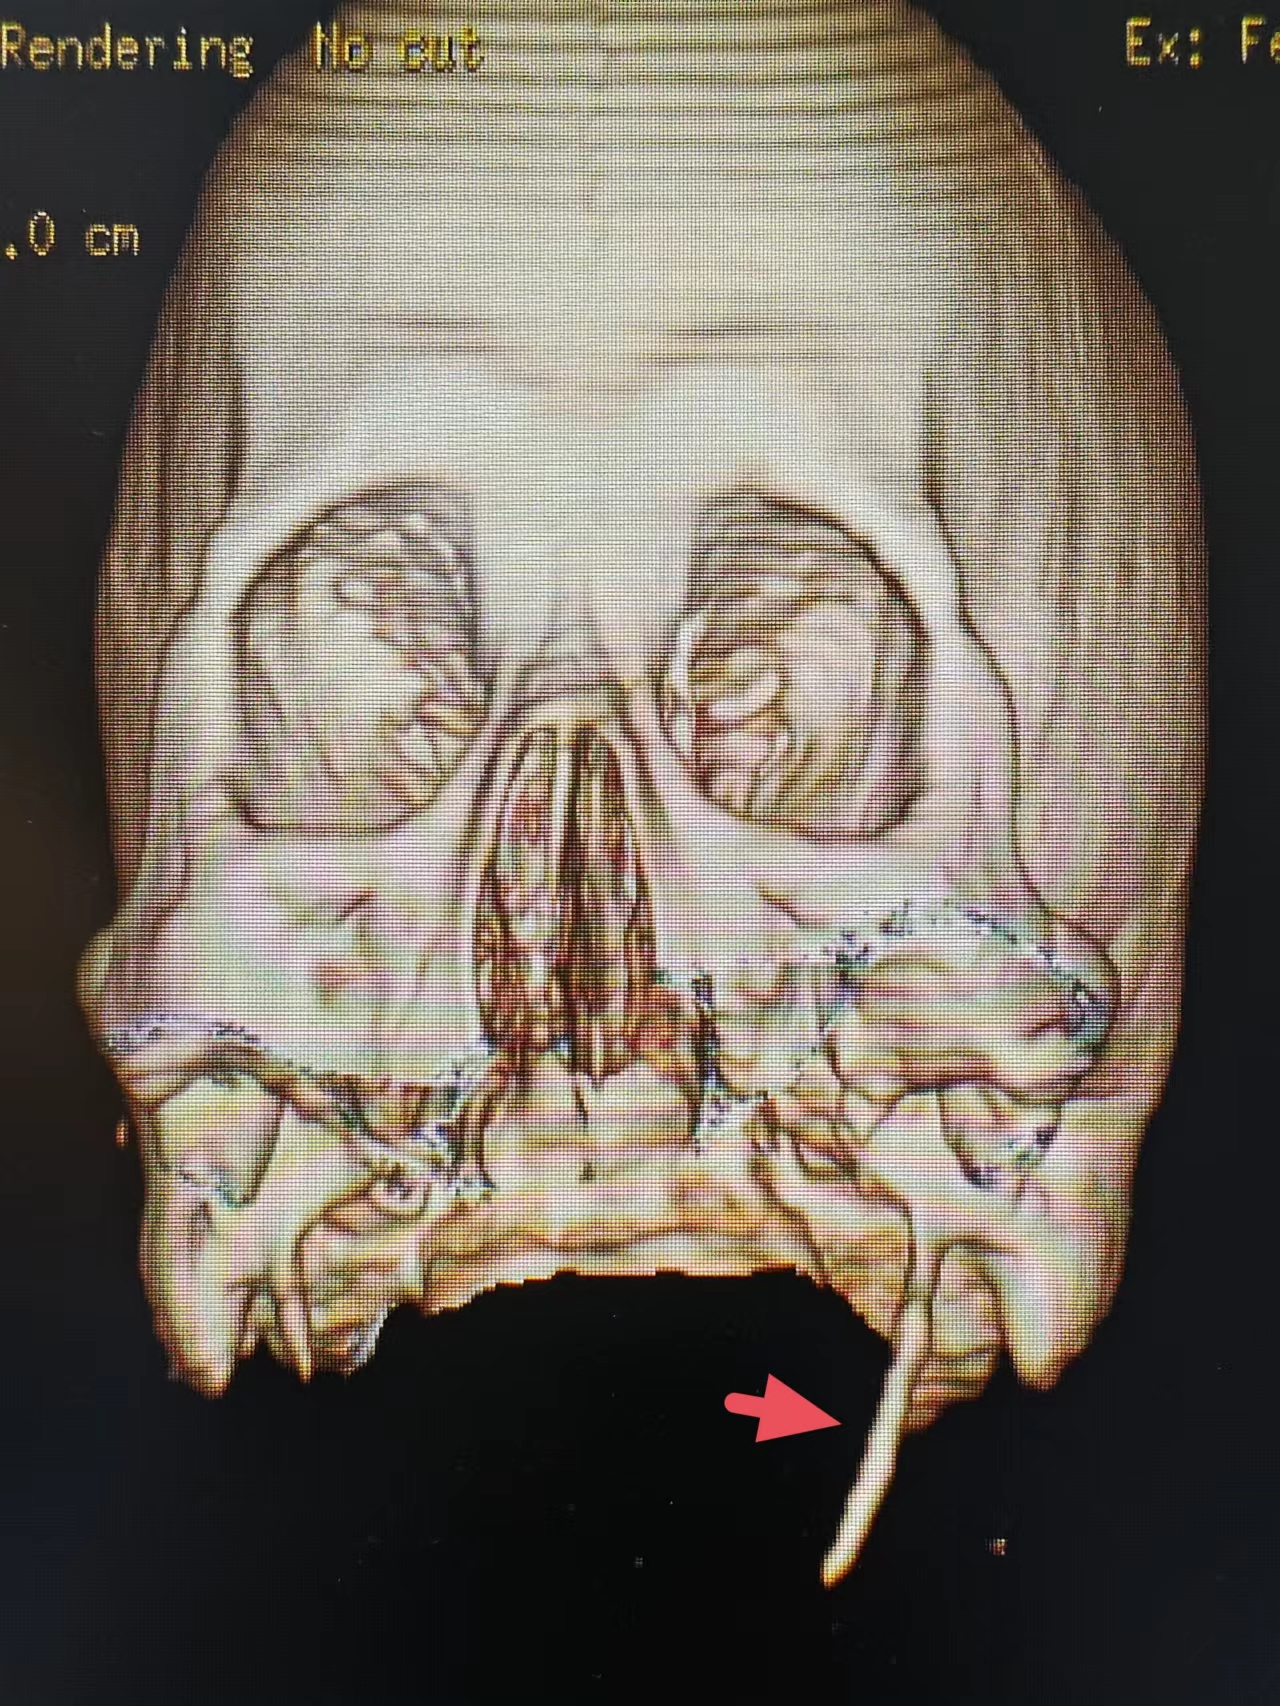

一位患者 , 多年来一直觉得咽部有异物 , 辗转多地求医 , 吃了很多药都没有效果 , 我们通过MDCT三维成像检查出该患者左侧茎突过长 , 确诊茎突综合征 。

以头颈部疼痛就诊的茎突综合征患者易被误诊为咽炎、外耳道炎、淋巴结炎等疾病 。 因此 , 对年龄20岁以上的患者 , 如果有单侧或双侧的咽异物感、咽痛 , 同时有耳、头疼的病史 , 特别是转头加重的 , 均应考虑茎突综合征可能 。 应行查体及影像学检查 , 特别是多排螺旋CT三维成像检查 , 可以清晰立体的显示茎突的长度、角度、与周围血管、神经组织的关系 。

在多排螺旋CT出现以前时代 , 一般通过茎突正侧位X线片诊断茎突综合征 。 X线片缺点是投照技术困难 , 很难照出一张清晰的茎突影像 , 重叠组织多 , 不能多角度、多方位观察 , 很难全面准确的观察茎突 。 多排螺旋CT广泛应用于临床后 , MDCT三维成像可以清晰立体全面准确地观察茎突长度、角度 , 与周围血管、神经的关系 。